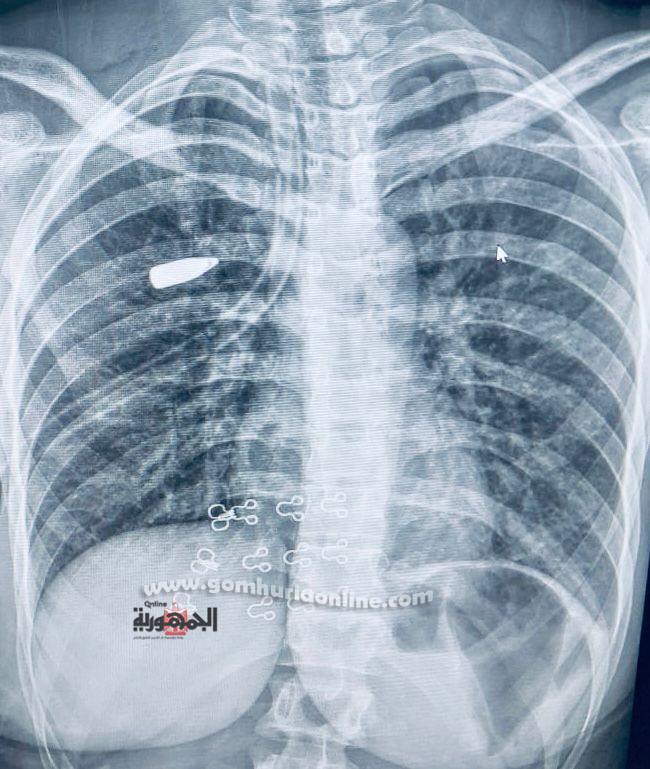

تمكن فريق طبي  بمستشفى القلب بجامعة أسيوط من استخراج مقذوف ناري مستقر في أغشية الرئة لفتاة عشرينية، وذلك باستخدام تقنية منظار الصدر الجراحي المتطورة.

وعلى الفور، قام الفريق الطبي بإجراء الفحوصات والإجراءات اللازمة، والتي كشفت عن استقرار المقذوف الناري داخل أنسجة الرئة اليمنى.

وتم مناظرة دقيقة للحالة وإجراء الأشعات اللازمة التي أكدت استقرار المقذوف بين أغشية الرئة، ليقوم الفريق الطبي بإجراء جراحة دقيقة للغاية، وتم استخراج المقذوف الناري بنجاح باستخدام منظار الصدر الجراحي من خلال فتحة جراحية لا تتعدى 2 سم، مما ساهم في الحفاظ على سلامة الرئة وتقليل التلف إلى أدنى حد، بالإضافة إلى الحفاظ على الشكل الجمالي لجدار الصدر.